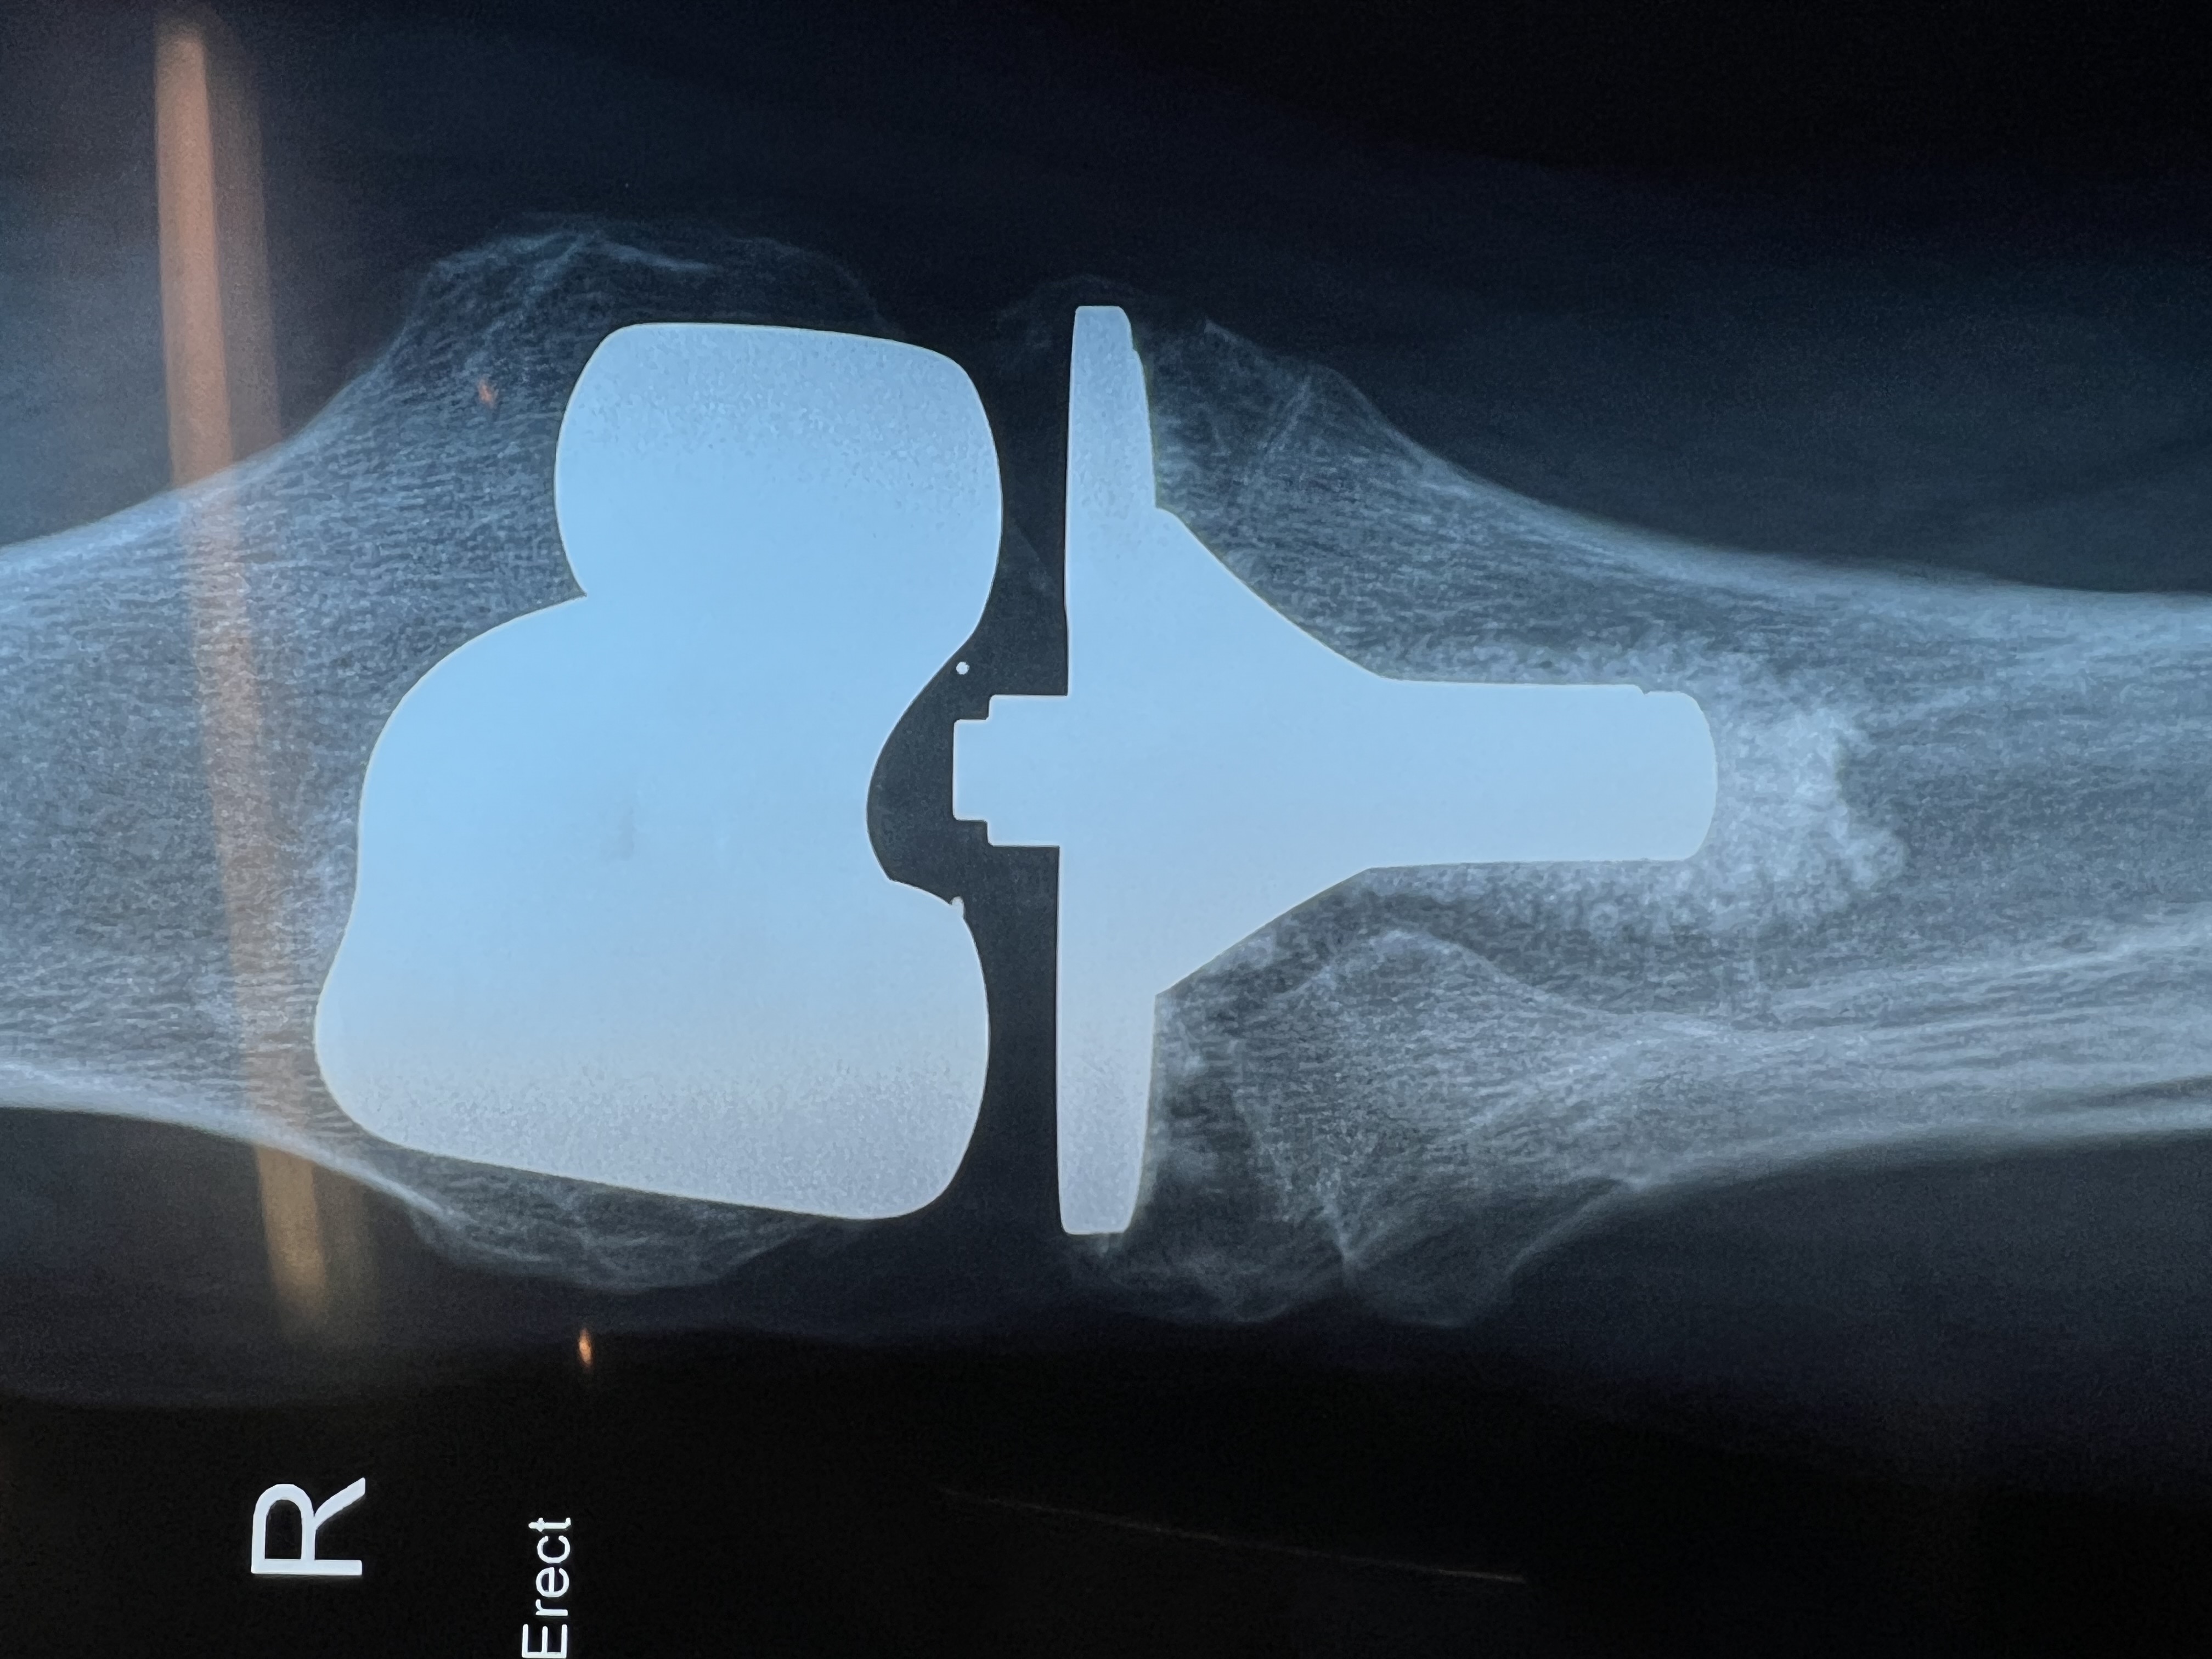

Total Knee Replacement

Knee TKR close B Braun AS Emotion Total Knee Replacement showing Gold ceramic coating of Zirconium Nitride

Total Knee Replacement: What to Expect

A total knee replacement is a surgery to replace a damaged or worn-out knee joint with an artificial one. It is often done for people with severe arthritis or injuries that cause chronic pain, stiffness, and difficulty walking.

1. Removes the damaged bone and cartilage from the ends of the femur and tibia.

2. Shapes the bones to fit the artificial joint.

3. Attaches the new knee joint, made of metal and plastic, to restore smooth movement.

4. Tests for proper movement and stability before closing the incision.